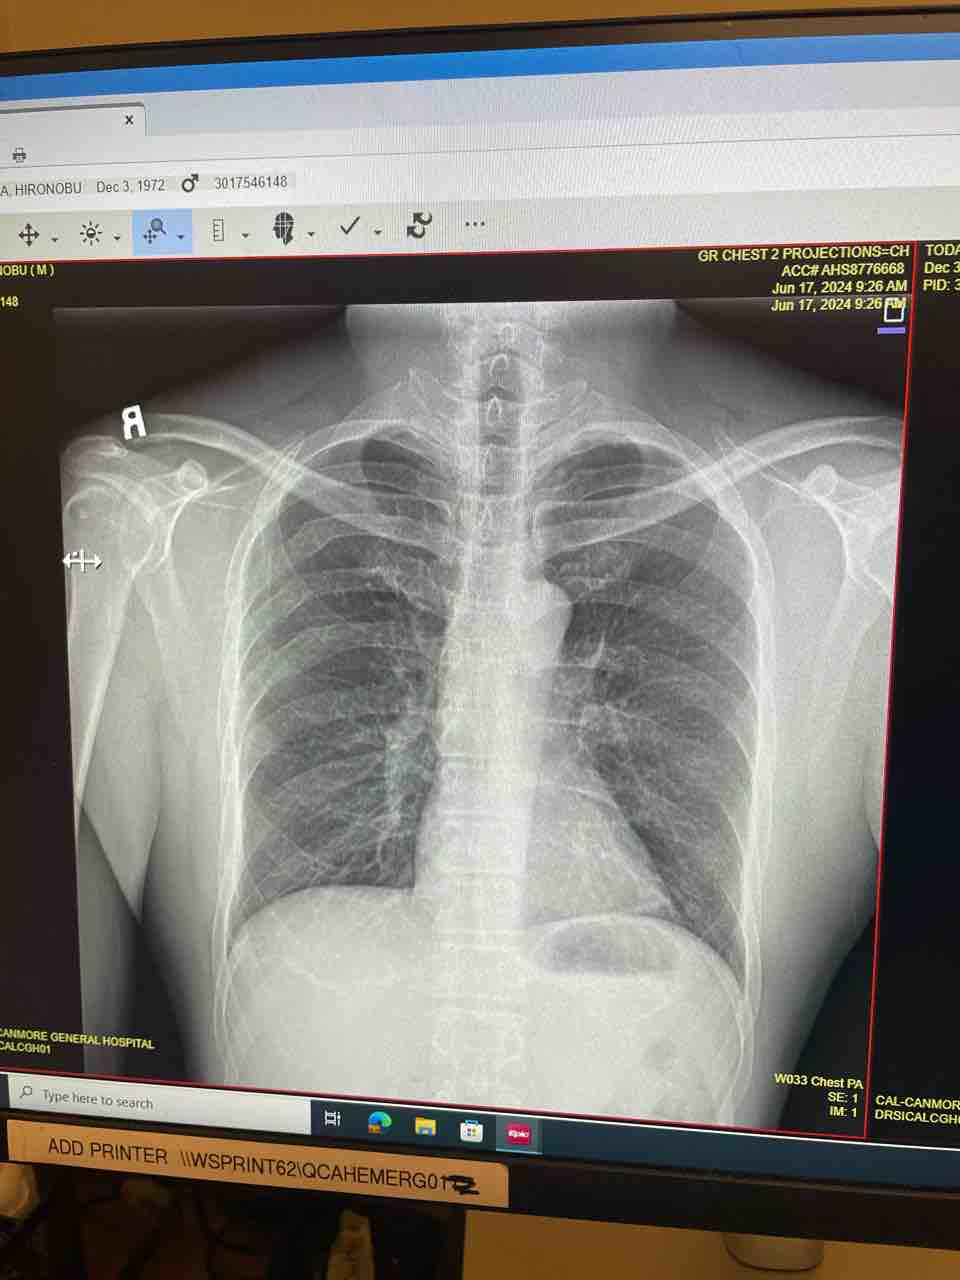

肋骨マニア再び。 2024-06-18 08:41:20 わしじゃけど。

またやっちゃった。

家の中にあるクライミングジムで軽くボルダリングしてて、

いつもより違う動きでホールドを取ろうとしたら、

掴んでいたホールドのねじが緩んでいて、

クルっと回ってしまい、

そのまま落ちた。

いつもならマットを敷いているはずなのに、

こういう時に限って敷いてないところに。。。

落ちたときは、呼吸が十数秒できなくて、

「これはやってしまった!!」

と思ったが、しばらくして浅い呼吸ができるようになって

その場にうずくまること小一時間。

軽い臨死体験をまた経験してしまった。

とてもじゃないがそのまま病院に行けるような状態ではなかったので、

しばらく休んで、病院へ。。。

病院に入ったら、受付の人がわしを見るなり、

Emergencyへの入り口を指さす。

そのまま救急病室そして、レントゲン。

IMG_2687

ドクターは、

内臓には異状ないし、折れてないから

数か所にヒビ入ってるね。

って、このレントゲンでわかるの?

見ても全然わからんが。。。

とりあえず、職場に提出する診断書を作ってもらい、

全治数週間、痛みがなくなったら職場復帰できるよ。